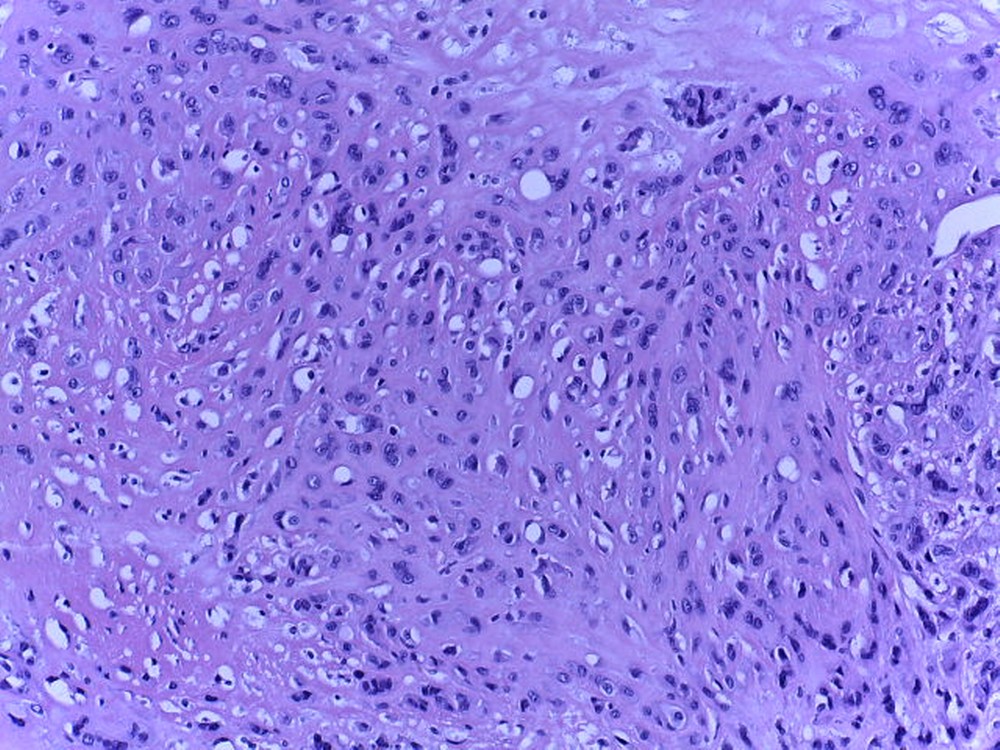

Caso del mes de Febrero de 2021

Mujer de 39 años con tumor en tobillo.

Respuesta:

Hemangioendotelioma epitelioide.